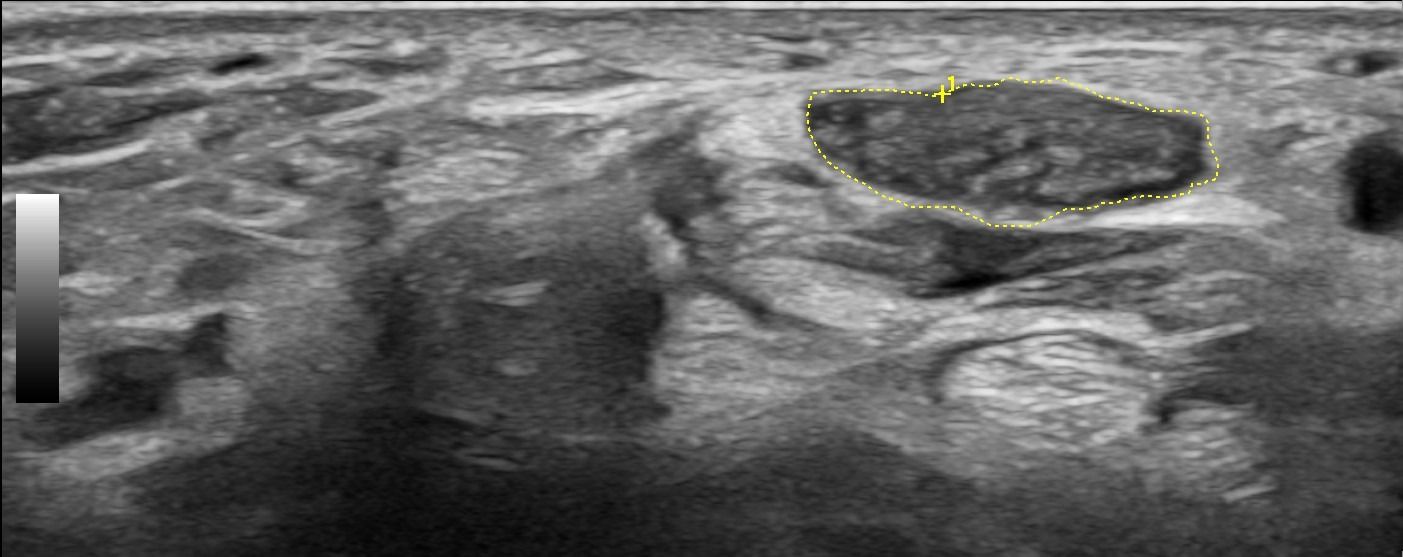

Hand Ultrasound examines joints, tendons, ligaments, nerves, and soft tissues of the hand. Pathologies that can be diagnosed by Hand Ultrasound are numerous, including:

Rheumatic Diseases

- Rheumatoid Arthritis

- Psoriatic Arthritis